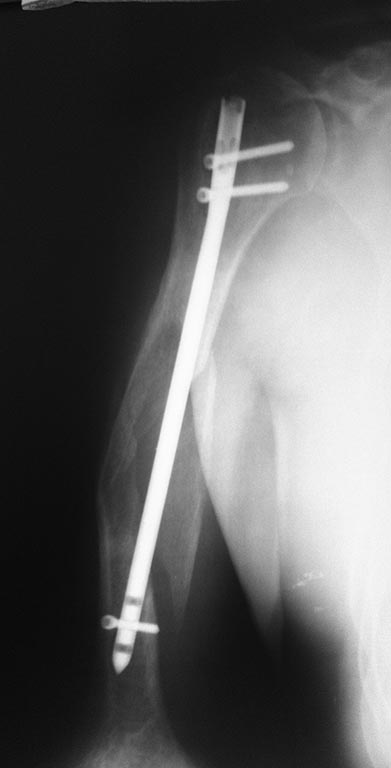

Ложный сустав плеча после БИОС |

Здравствуйте, уважаемые коллеги! Хотелось бы спросить, о вариантах возможного лечения. Мужчина, 57 лет, плотного телосложения. Тяжелых сопутствующих нет. Оперирован в ноябре 2014 года. В настоящий момент сохраняется патологическая подвижность. Честно говоря, пациента это не сильно беспокоит (не без труда уговорил его прийти на след. неделе). Есть в наличии штифты, пластины и аппарат при необходимости соберем.Заранее благодарен!

Интересно, в чем проявляется патологическая подвижность? Лизиса вокруг винтов вроде не видно. Пациента это не сильно беспокоит (что - "это"?). Непонятно, что в данном случае патологически двигается? Было бы неплохо увидеть другую проекцию.

Очень внимательно - лизис виден. Нужна другая проекция, так как конец стержня на уровне н/3 (физиллогический изгиб плеча). Рассверливание обязательно. Это в случае БИОС. Пластина более трвматично, в рубцовых тканях...

Некорректное стояние импланта, недостаточная длинна и отсутствие стабильной фиксации короткого(дистального) отломка.Ре БИОС, с рассверливанием канала, с использованием штифта больших диаметра и длинны, отталкивающих спиц, если потребуется, дистальная фиксация минимум 2-мя винтами, в случае достаточного контакта основных отломков и учитывая атрофический характер ложного сустава проксимальная блокировка по компрессионной схеме + осевая нагрузка (трость). Результат должен быть хорошим.